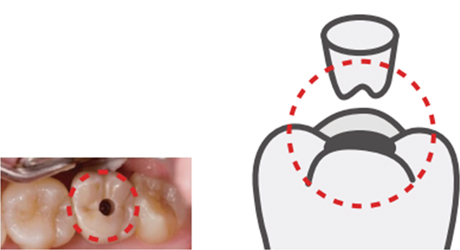

나사형 보철

나사형 보철보철물을 나사로 고정시키는 형태로 고정과 사용 중 수리가 편리하다는 장점이 있습니다. 하지만 나사가 헐거워지며 보철물이 흔들리거나 나사가 빠지는 경우가 생기며 나사를 조이기 위한 구멍이 심미성을 떨어뜨리는 단점이 있습니다.

나사형 보철

나사형 보철 -